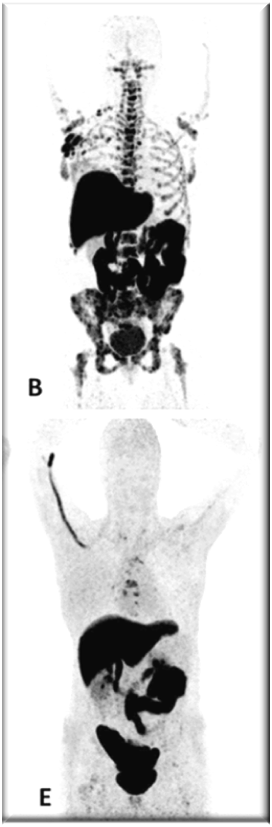

PET images of two patients with metastatic invasive lobular carcinoma responding (A-C) and not responding (D-F) to palbociclib + letrozole

Adapted with permission from Boers, J., et al. European Journal of Cancer. 2020; 126: 11-20

Upper row responder: (A) Baseline [18F]FDG-PET shows pathological uptake in axillary lymph nodes (right side) and in nearly all vertebrae and pelvic bones. (B) Baseline [18F]FES-PET with pathological ER expression in the axial skeleton (vertebrae, pelvic bones, proximal humeri and femora) and in axillar lymph nodes. (C) [18F]FDG-PET after 8 weeks shows almost complete metabolic response. The patient has been on treatment for more than 70 weeks.

Lower row non-responder: (D) Baseline [18F]FDG-PET shows pathological uptake in multiple skeletal lesions. (E) Baseline [18F]FES-PET with only some increased ER expression in thoracic vertebrae. (F) [18F]FDG-PET after 8 weeks shows no metabolic response, with some increase in the pathologic uptake in the multiple skeletal lesions.